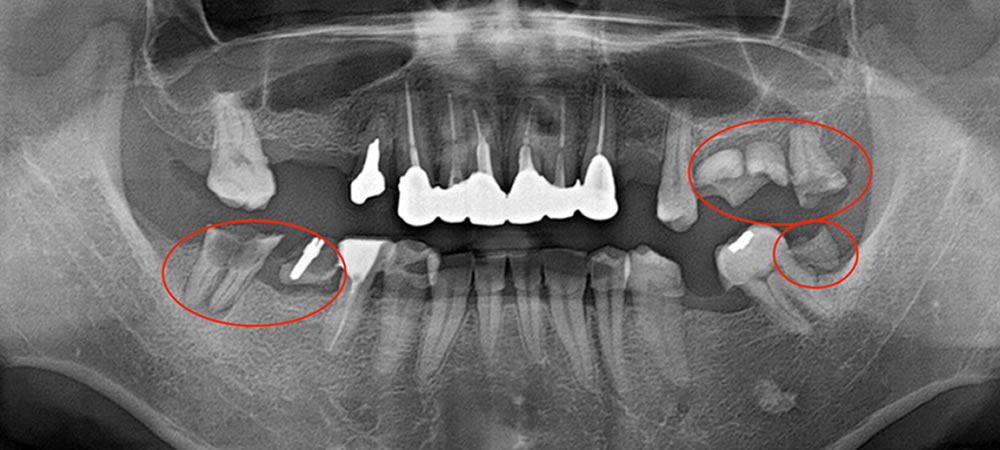

保存困難で抜歯をした部位は写真の赤丸です。

下顎の歯の本数がもともと少なく、上顎歯列弓と下顎歯列弓の大きさにつじつまが合わない状態でした。下顎両側3番と2番の癒合歯(2本の歯がくっついている状態)、あるいは先天欠如によるものと考えられます。